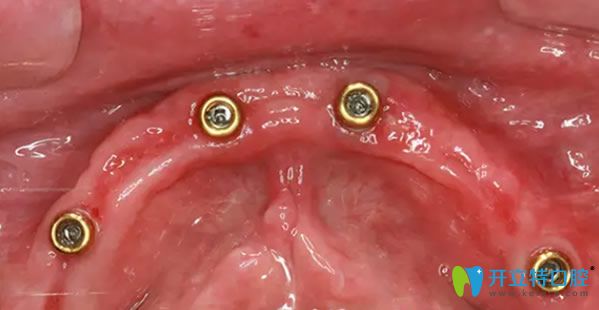

到院后,譚院長(zhǎng)通過CT進(jìn)行數(shù)據(jù)采集,電腦精密計(jì)算人工牙根的植入位置,精準(zhǔn)制定種植方案,先把種植體種在牙槽骨內(nèi),然后再等恢復(fù)。外婆年紀(jì)大了,父母總擔(dān)心,種植過程中疼痛怕她承受不了。譚院長(zhǎng)說我們的擔(dān)心都是多余的,會(huì)緊張那是必然的,手術(shù)是通過高氧恢復(fù),能夠讓高齡老人種牙后得到更好的調(diào)養(yǎng),真正實(shí)現(xiàn)無痛種牙。

種植前CT效果: